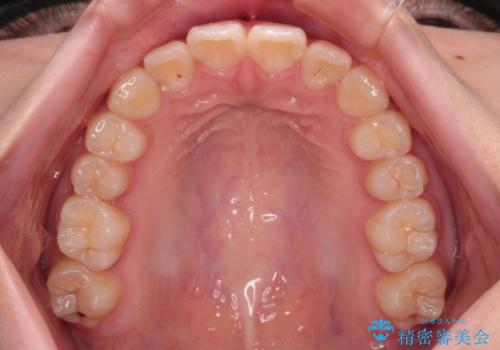

- 上下前歯のねじれを気にして来院された患者様です。

ワイヤー矯正でもマウスピース矯正でも対応可能でしたが、マウスピース矯正の自己管理が面倒であること、上顎前歯の捻転が著しいことから、ワイヤー矯正での治療を希望されました。